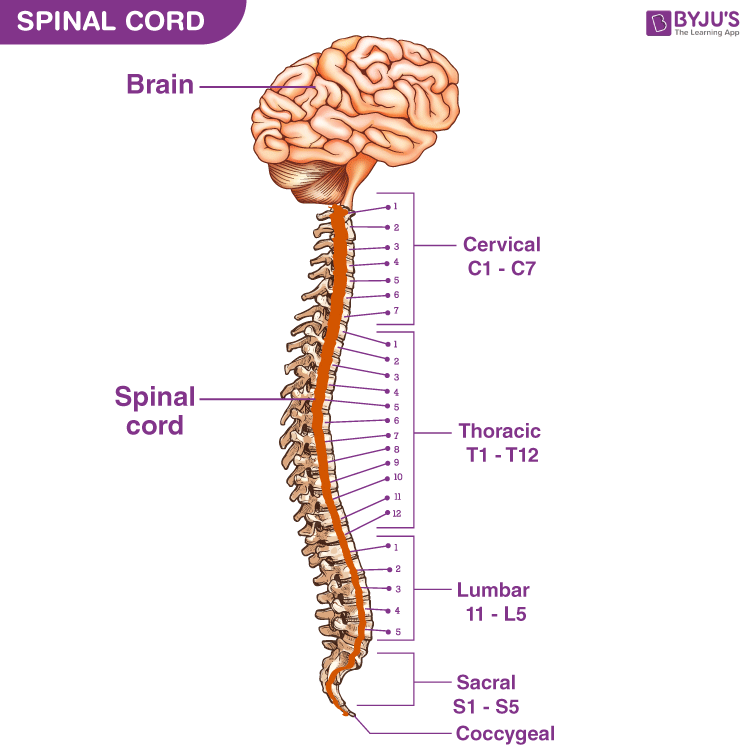

silikonsheet.blogg.se – Spine diagram

Anatomy of Spinal Cord Injury – Treatment, Complication – Rxharun

Spinal Cord Injury Levels | Bone and Spine | Spinal cord injury, Spinal …

What is a Spinal Cord Injury (SCI)? – First Aid for Free

Diagram | Spinal Cord Injury | Pinterest | Spinal Cord Injury and Cords

Spinal Cord Lesions with MS | Multiple experienceS | Spinal cord …

Pin by Allison Atwill on OT Grad in 2021 | Spinal cord, Spinal cord …